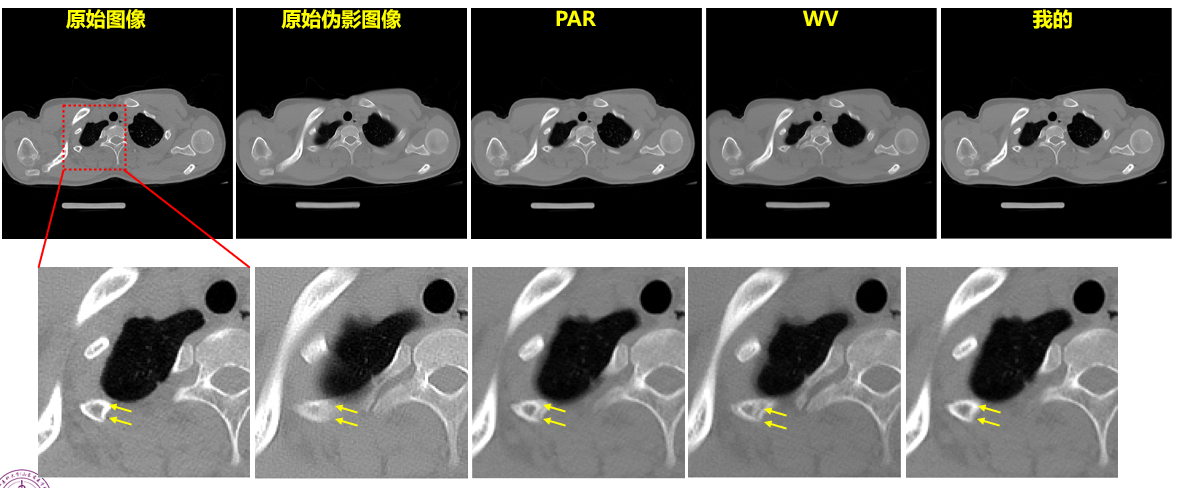

环状伪影的去除与传统方法的比较

结果图像对比